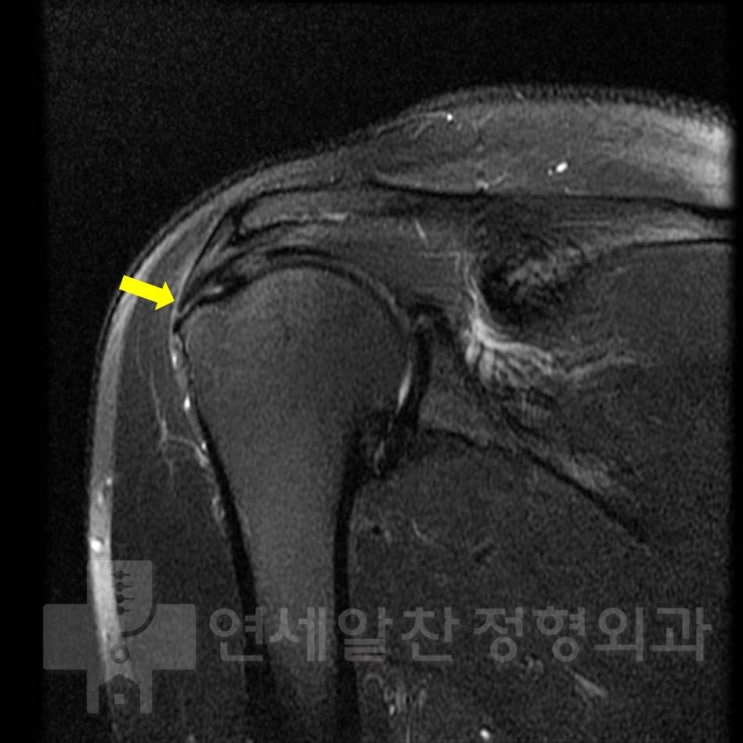

어깨 회전근개 파열 : 보다 단단하게 봉합하는 이열봉합법

안녕하세요. 정형외과 전문의 이동규 입니다. 오늘은 회전근개 파열에서 관절경 수술시 더 단단하게 봉합하...